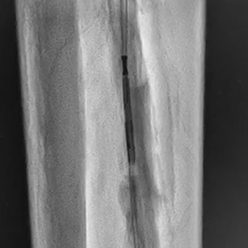

• Unique needle design / shape, axial protrusion or lateral protrusion selector, with excellent pushability and torqueability

• Highly stable support from a very low profile 4Fr catheter with a 0.018" catheter guidewire and 2.9Fr catheter with a 0.014" catheter guidewire

• Unique RO marker directly on the needle provides both radial and axial needle position information